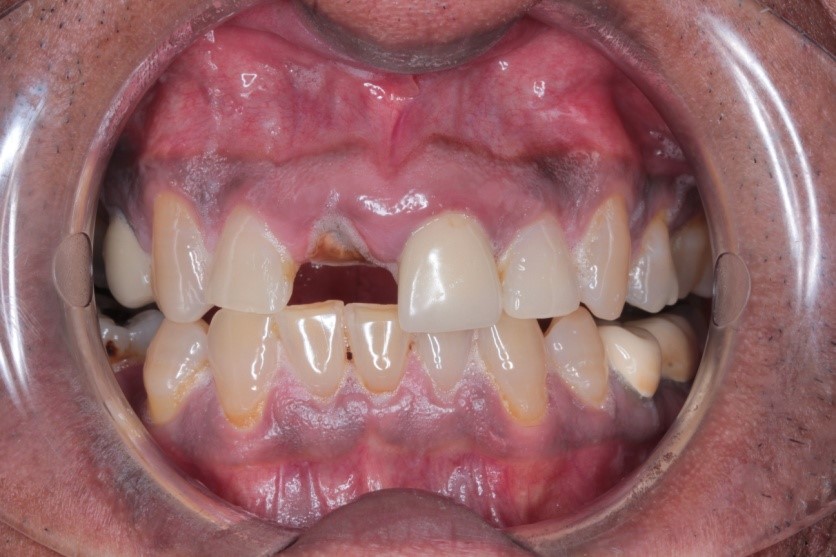

Beginning the treatment, the patient in question came to Dr Bagasi with a missing upper right central incisor (UR1). The missing tooth caused the patient to develop problems with their self-image – ultimately leading to the patient becoming quite self-conscious. These are very common repercussions that result from a broken smile, as the patient can find it very difficult to live with missing teeth.

After the missing UR1 was thoroughly examined, (while also proving a further examination of the patient’s general and oral health) Dr Bagasi suggested three potential methods for replacing the missing tooth. These were: